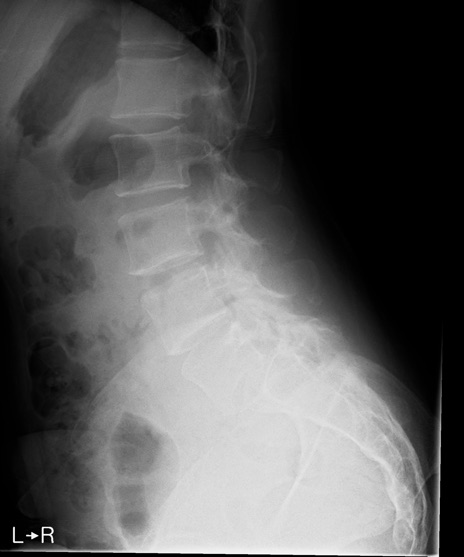

【整形】TIPS症例4 腰椎レントゲン(側面像)

【症例】30歳代男性

【主訴】腰痛、両大腿後面の痛み

【現病歴】高校時代に●●を指摘されたが経過観察されてきた。体動時の腰痛があり、長時間立位、坐位にて両大腿後面の痛みを感じる。外来にて経過観察されてきたが改善ない。

【身体所見】SLR 60/60、TA5/5,EHL 5/5,FHL 5/5、psoas 5/5、quad 5/5、PTR+/+、ATR+/+、babinski-/-、長時間歩行で症状あるがなんとか歩いている。安静時痛なし。体動時、長時間立位、坐位にて症状あり。

異常所見と診断は?